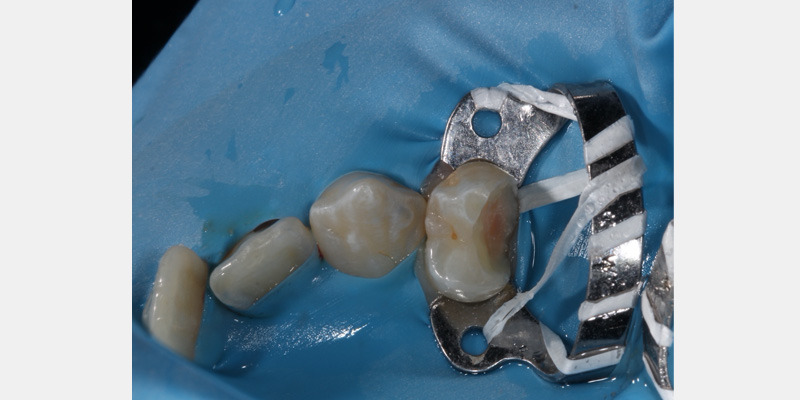

One of my most significant issues was using the wrong clamp. There are many different clamps on the market, each of which can work well when used correctly. The two main categories of clamps are “winged” and “wingless.” Winged clamps have an extra lip built into the clamp design that can aid in retracting the dam, but they are bulkier than wingless clamps.

Both wingless and winged clamps are helpful. Selecting one over another is solely a matter of preference. In general, I’ve found the following clamps to be most useful in our day-to-day practice:

- W8A for maxillary molars

- 14 A or W14 for mandibular molars

- 12A for mandibular right molars, 13A for mandibular left molars

- 2 for premolars

- 9 for anteriors where retraction on the facial is needed for cavity preparation

Another common issue is the leakage of oral fluids through the dam. One way to mitigate this is by selecting the proper-sized holes for the teeth being isolated.

The first, largest hole is useful for molars holding the clamp. The second largest hole is useful for unclamped molars or clamped premolar teeth. The third hole is suitable for premolars, the fourth for canines and maxillary central incisors, and the fifth and smallest is useful for maxillary lateral incisors and mandibular incisors.

Placing the dam intraorally can also present a challenge since the dam can fold upon itself when trying to place it on the teeth. To simplify this, the dam can be attached to the frame before it is placed in the mouth. This keeps the dam taunt, making it easier to facilitate placement intraorally.